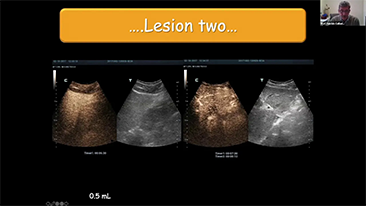

Aparaty ultrasonograficzne z serii Resona, dzi?ki szerokiej gamie za pomoc? wszechstronnych sond do r√≥?nych zastosowaŇĄ i wydajnych narz?dzi do zastosowaŇĄ klinicznych, pomagaj? U?ytkownikom stawia? dok?adniejsz? i efektywniejsz? diagnoz? oraz ocenia? wyniki.

Produkty do obrazowania ogólnego